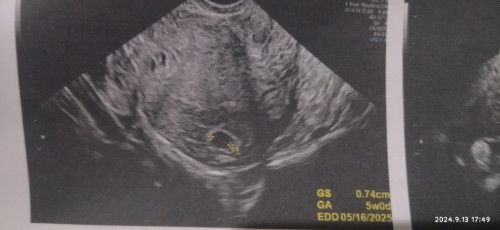

No Yolk Sac / fetal Pole

7 weeks base on LMP pero kanina pagcheck sa TVS is 5weeks palang daw laki kso wla makita na baby 😭 worried na po ako nagtatake nmn ako ng vitamins

LMP JULY 26, 2024

Ano po ibig sabihin?

walang pang nakitang fetus due to early pregnancy. repeat TVS after 2 weeks.